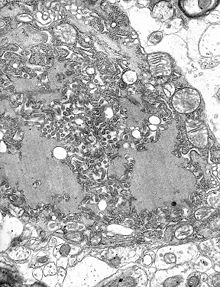

Once within a muscle or nerve cell, the virus undergoes replication. The trimeric spikes on the exterior of the membrane of the virus interact with a specific cell receptor, the most likely one being the acetylcholine receptor. The cellular membrane pinches in a procession known as pinocytosis and allows entry of the virus into the cell by way of an endosome. The virus then uses the acidic environment of that endosome and binds to its membrane simultaneously, releasing its five proteins and single strand RNA into the cytoplasm.

The L protein then transcribes five mRNA strands and a positive strand of RNA all from the original negative strand RNA using free nucleotides in the cytoplasm. These five mRNA strands are then translated into their corresponding proteins (P, L, N, G and M proteins) at free ribosomes in the cytoplasm. Some proteins require post-translative modifications. For example, the G protein travels through the rough endoplasmic reticulum, where it undergoes further folding, and is then transported to the Golgi apparatus, where a sugar group is added to it ( glycosylation).

Where there are enough proteins, the viral polymerase will begin to synthesize new negative strands of RNA from the template of the positive strand RNA. These negative strands will then form complexes with the N, P, L and M proteins and then travel to the inner membrane of the cell, where a G protein has embedded itself in the membrane. The G protein then coils around the N-P-L-M complex of proteins taking some of the host cell membrane with it, which will form the new outer envelope of the virus particle. The virus then buds from the cell.